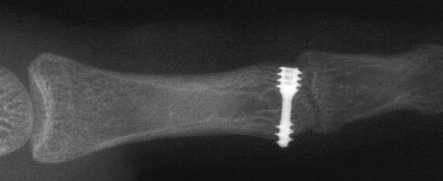

Reduction and fixation with the mini Herbert screw...

Click for larger image

This was a bit of a struggle because of the screw size and delay in fixation. I think a better technique is using two microscrews, as in this patient....